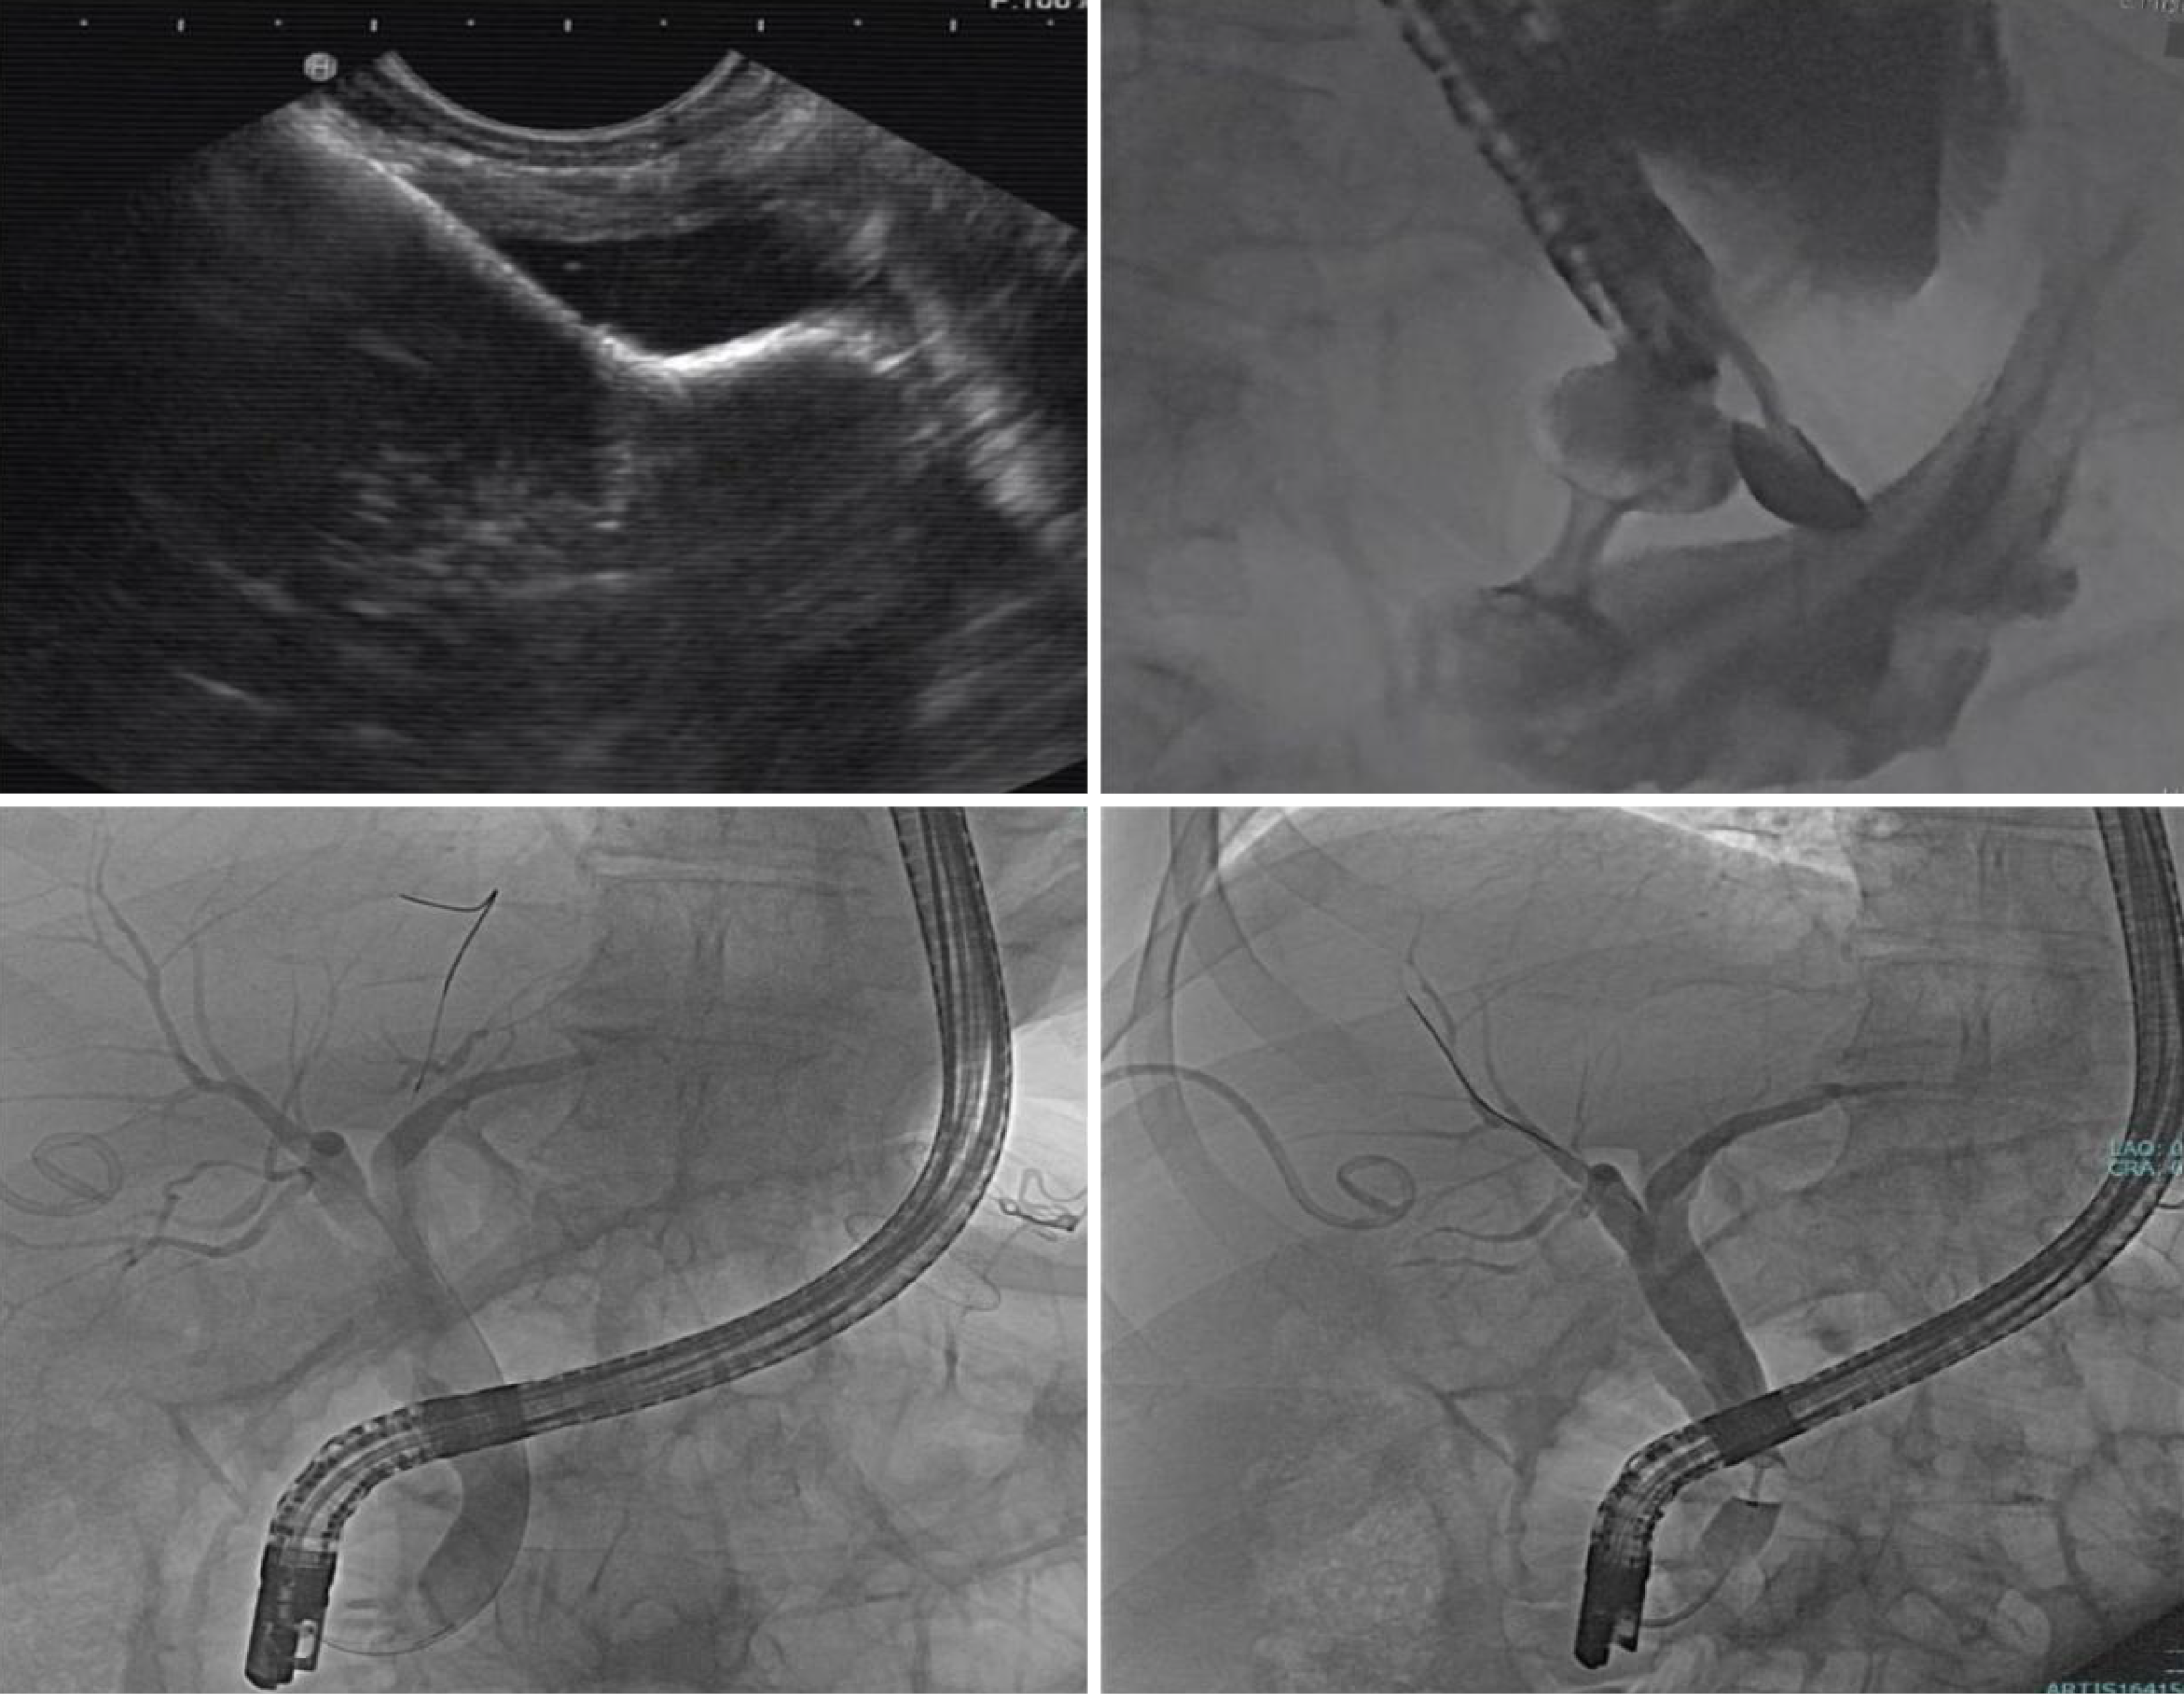

Figure 3

Endoscopic ultrasound directed transgastric endoscopic retrograde cholangiopancreatography.